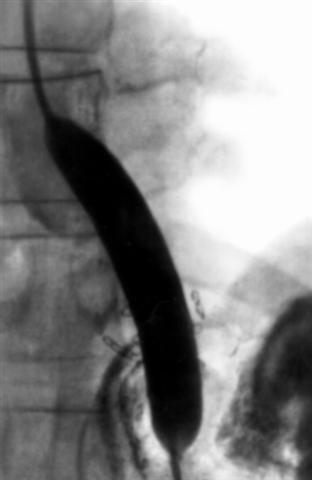

Рис. 3б). Ренгенограммы пищевода при сужении его поддиафрагмального сегмента: в момент баллонной дилатации.